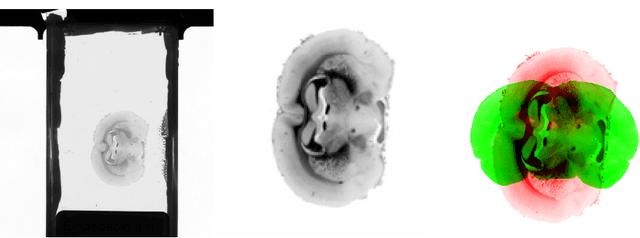

Abstract:3D reconstruction of the fiber connectivity of the rat brain at microscopic scale enables gaining detailed insight about the complex structural organization of the brain. We introduce a new method for registration and 3D reconstruction of high- and ultra-high resolution (64 $\mu$m and 1.3 $\mu$m pixel size) histological images of a Wistar rat brain acquired by 3D polarized light imaging (3D-PLI). Our method exploits multi-scale and multi-modal 3D-PLI data up to cellular resolution. We propose a new feature transform-based similarity measure and a weighted regularization scheme for accurate and robust non-rigid registration. To transform the 1.3 $\mu$m ultra-high resolution data to the reference blockface images a feature-based registration method followed by a non-rigid registration is proposed. Our approach has been successfully applied to 278 histological sections of a rat brain and the performance has been quantitatively evaluated using manually placed landmarks by an expert.